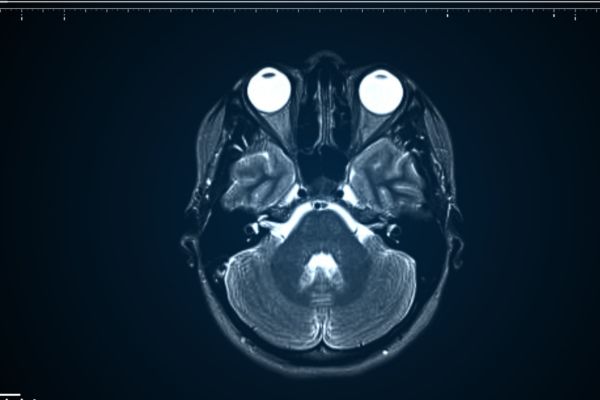

Un profesional puede utilizar pruebas de imagen para determinar la localización y el tamaño del craneofaringioma. Las pruebas de imagen incluyen la resonancia magnética (RM) y la tomografía computarizada (TC). En ambas pruebas se suele aplicar un contraste para mejorar la claridad de la imagen.

Dado que la mayoría de los craneofaringiomas presentan una acumulación de calcio, las tomografías computarizadas son muy útiles para obtener imágenes de este tipo de tumor, ya que son especialmente buenas para visualizar tumores con acumulación de calcio.